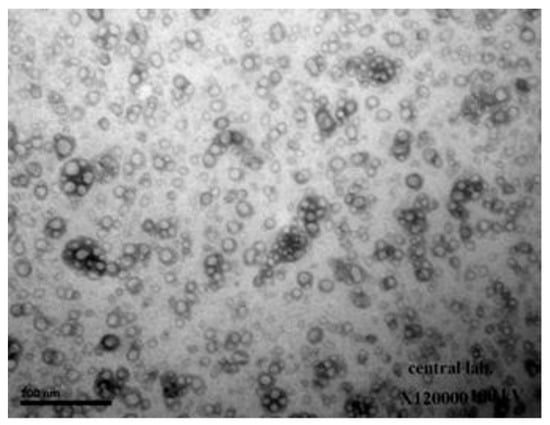

2.4.2. Determination of Morphology